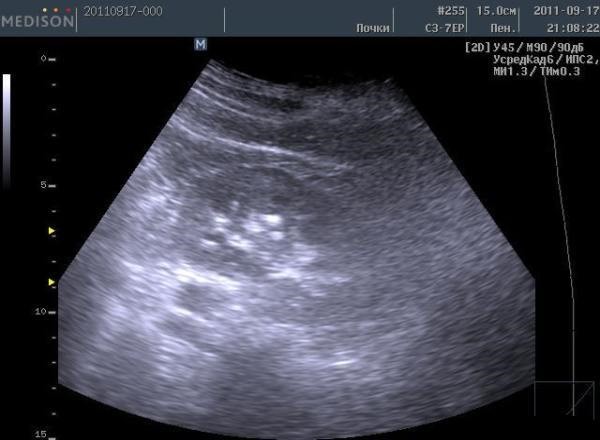

Иногда во время ультразвукового исследования у пациента, преимущественно у мужчин в молодом возрасте, доктор видит в тканях яичек рассредоточенные белые точки. Так выявляется, порой совершенно случайно, тестикулярный микролитиаз.

На данный момент ультразвуковое исследование – это наиболее точный и основной метод диагностирования тестикулярного микролитиаза. При этом стоит обращать внимание, какие сканеры используются для диагностирования. Дело в том, что старые аппараты УЗИ не достаточно оснащены оптической оснасткой и выявляют лишь крупные кальцификаты, то есть, упуская из виду мелкие камешки, которые только начинают образовываться. А это значит, что первый этап заболевания пропущен.

Микрокальцинаты — это крошечные камешки, образующиеся из кальция и эпителиальных клеток семенных канальцев. Их можно обнаружить на УЗИ, где они визуализируются в виде белых пятен на черном фоне. Это дало болезни название «синдром звездного неба».